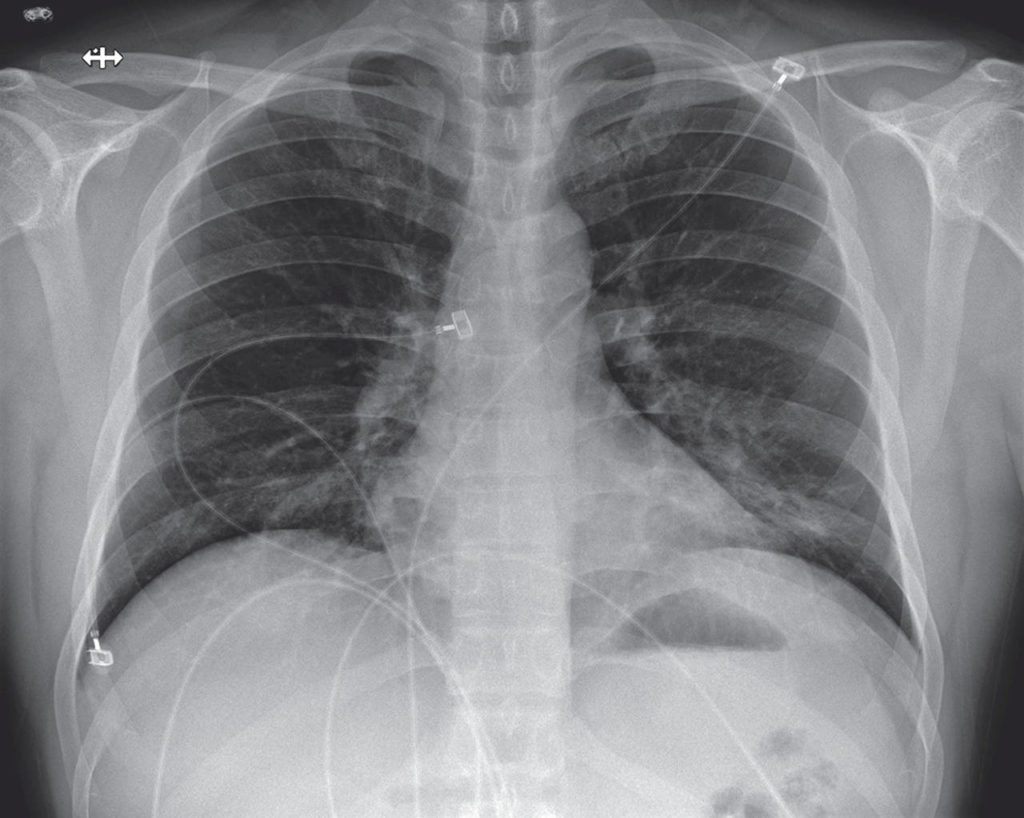

The article details the patient’s symptoms — everything from fatigue, nausea, diarrhea to a runny nose — over time and graphs his lab results. It shows X-rays of his lungs.